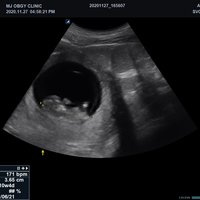

Mit dem X-CUBE 90 beginnt ALPINION eine neue Generation an Farbdopplersystemen, die X- CUBE Serie. Mit Bildverarbeitungstechnologien eines Premiumsystems und neuen Breitband- Schallköpfen mit X + Crystal Signature™ Technologie wartet das neue X-CUBE 90 auf.

Neben der hohen Bildqualität liegt ein weiterer Fokus auf der Vereinfachung und der Anpassung der Bedienung des Ultraschallgeräts. Individuell programmierbare Workflows und ein erweitertes Spektrum an automatisierten Messungen ermöglichen ein schnelleres und genaueres Arbeiten in jeder Situation.

Volumen Konvex-Sonden

• SVC1-8H (1-8 MHz) für Ultraschalluntersuchungen in Bereichen Abdomen, Geburtshilfe, Gynäkologie, Urologie, Pädiatrie, EM